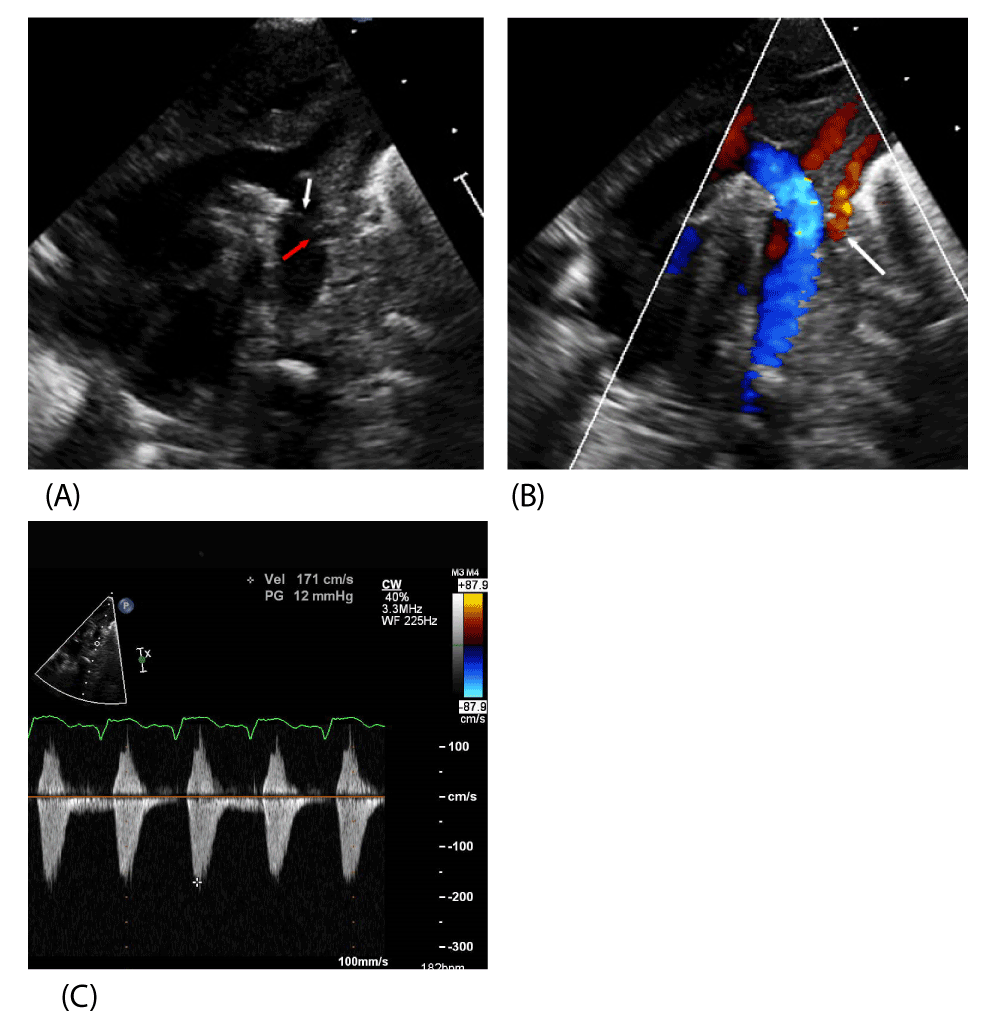

| Figure 2: A. 2D TTE performed after coarctation repair. The origin of the LSA is widely patent (red arrow). The arch repair is widely patent and the suture line is clearly visible (white arrow). B. 2D TTE with color Doppler interrogation demonstrating laminar flow in the left subclavian artery (white arrow). B, C. Color Doppler snows laminar flow in the descending aorta and spectral Doppler velocities are normal indicating no residual coarctation. Key: 2D TTE – two dimensional transthoracic echocardiogram, LSA – left subclavian artery. |